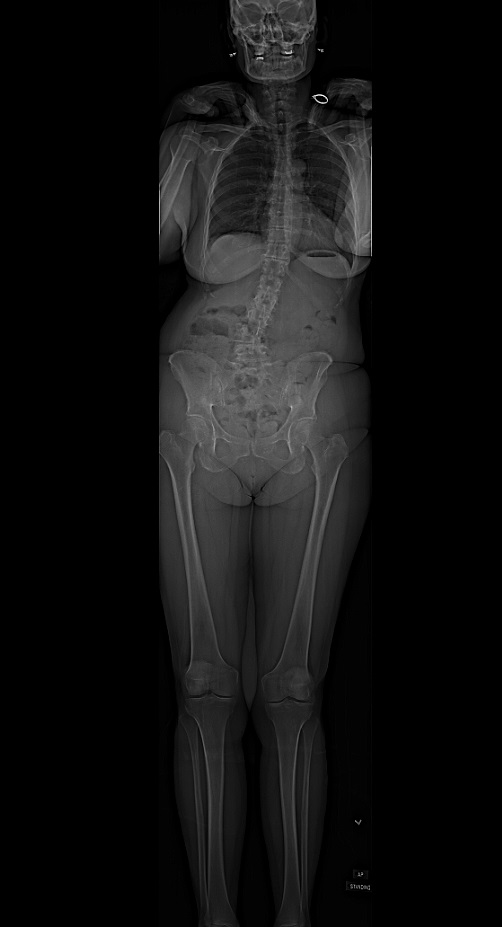

I can’t say enough positive things about Dr. Schwab, his team, and HSS. In December 2017, I had spinal fusion surgery from L-4 to S-1 to correct degenerative scoliosis, spondylolisthesis, and stenosis. I had experienced nerve pain and spasms in my right hip and leg for 22 months. I found my way to Dr. Schwab in November 2017, after seeing numerous specialists and undergoing every conservative treatment such as epidural injections, physical therapy, and even chiropractic.

I saw two recommended specialists in my hometown, Atlanta, GA. I got two very different opinions — from a minimally invasive procedure to a posterior spinal fusion - but neither planned to correct the scoliosis. I was skeptical and confused. I decided to travel to a highly regarded medical center where I believed I would get the answer. I was stunned when they told me they wanted to do two surgeries, both anterior and posterior, correcting the scoliosis and fusing my spine from the mid-back to the sacrum. This would then require about a month in a rehab facility. And, they said I would not be healed enough in 6 months to pick up a baby from a crib!

Meeting Dr. Schwab and Debra Jacobs, nurse practitioner, and his office staff confirmed my impression. They reviewed my images and answered all my questions. I was relieved when Dr. Schwab recommended only one surgery, a two-level posterior fusion (L4 - S1). And, I was happy Dr. Schwab said I would be healed in time for my grandson’s arrival. My last question was, “How quickly can you do it?” Natalia and Dorota quickly and efficiently arranged all of the pre-op testing so I did not need to make another trip to NYC before the surgery. Dr. Schwab also diagnosed a hip bursitis which was adding to my discomfort and recommended an injection. They were able to schedule an appointment in radiology the following day and, of course, he was right - I experienced relief within 24 hours.